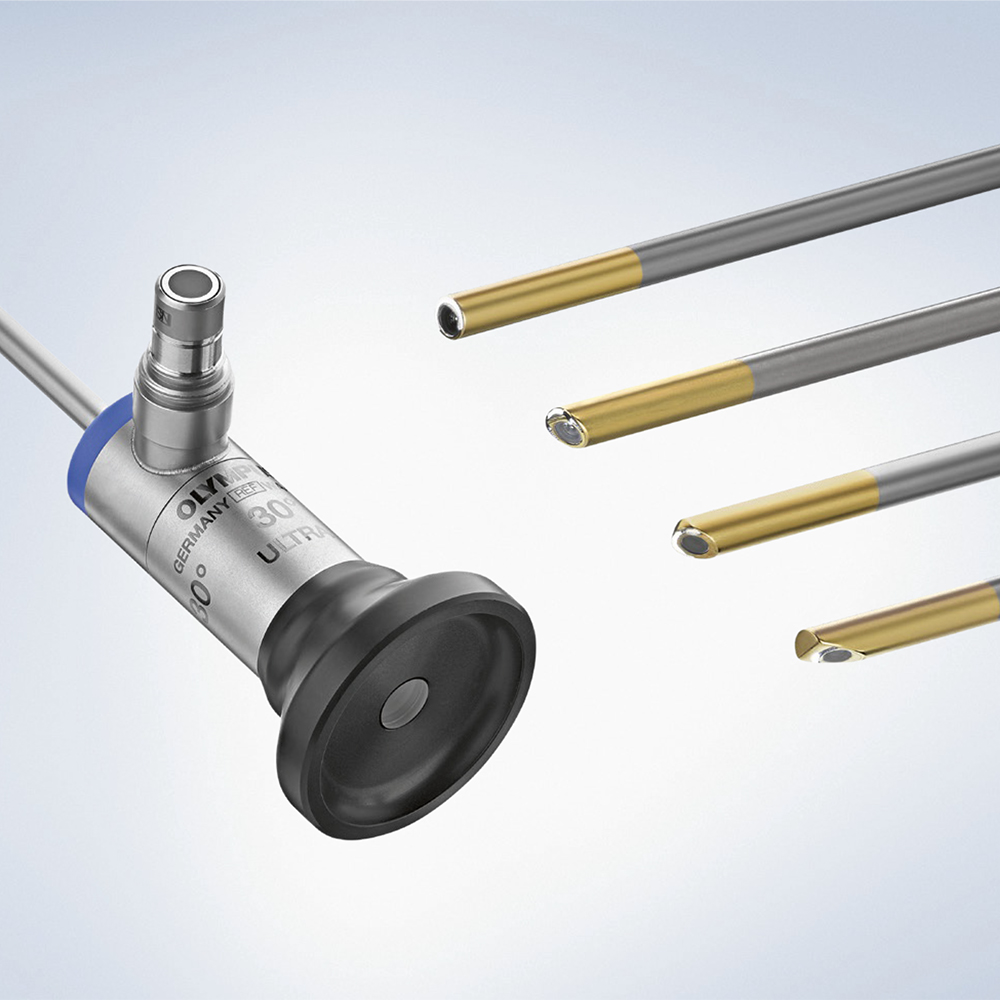

Microsystem

Microsystem Endoscopysystem